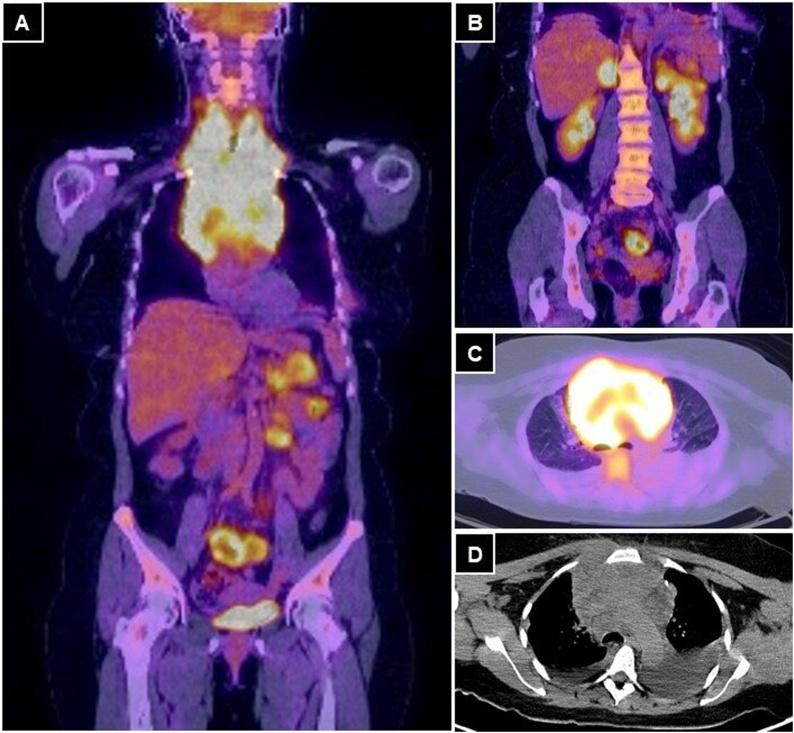

A 51-year-old woman with a history of PMBCL, hospitalized by a superior vena cava syndrome. PET-CT showed numerous lesions in the small intestine, pancreas, adrenal glands, and left kidney. During chemotherapy she presented abdominal symptoms, requiring an emergency laparotomy. On examination, six perforation sites were found in the small intestine. The pathology report revealed lesions compatible with PMBCL spread.

一名51岁有PMBCL病史的女性因上腔静脉综合征入院。PET-CT显示小肠、胰腺、肾上腺及左肾有多处病灶。化疗期间她出现腹部症状,需要紧急剖腹探查。检查发现小肠有六个穿孔部位。病理报告显示病灶与PMBCL播散相符。